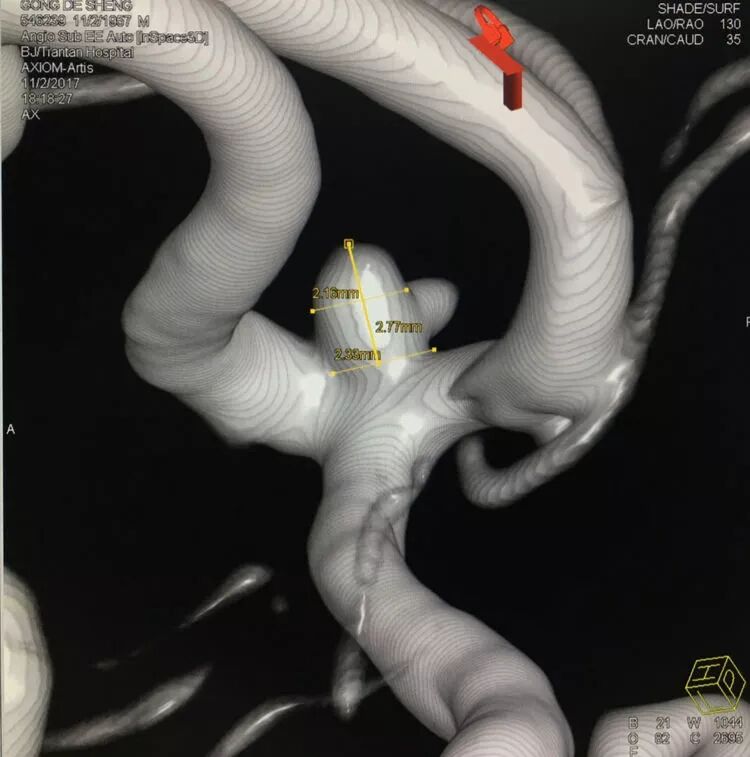

扁平状的前交通动脉瘤

仍然用双微管技术栓塞,一根直头微导管进入瘤体上部,另一根微导管头端塑成C形进入瘤体下部,分区栓塞该瘤